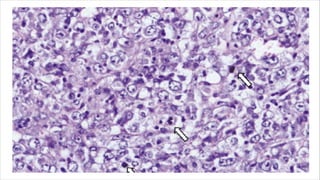

• Composed of nests or aggregates of cells separated by

fibrovascular septa

• Cells show degeneration and loss of cell cohesiveness

pseudoalveolar pattern

• Some cases especially in infants and children show more solid

sheets of malignant cells with loss of nesting , lack of pseudo

alveolar pattern

• Large or polygonal with eosinophilic granular cytoplasm

• Often with prominent nucleoli

• Nuclear pleomorphism including multinucleation and with rare

mitoses.